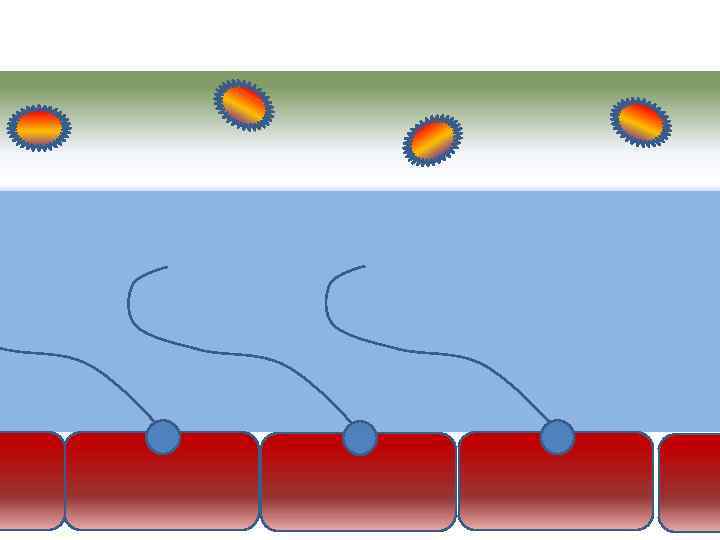

Движение клеток реснитчатого эпителия Движение вперед 1 – 3 Обратное движение 4 – 8

Движение клеток реснитчатого эпителия Движение вперед 1 – 3 Обратное движение 4 – 8

Механизм защиты легкого Слизь (зеленый цвет) нейтрализует и связывает патогенную флору(синий цвет) Слизь – это барьер между клетками и патогенной флорой Слизь – это транспортное средство

Механизм защиты легкого Слизь (зеленый цвет) нейтрализует и связывает патогенную флору(синий цвет) Слизь – это барьер между клетками и патогенной флорой Слизь – это транспортное средство